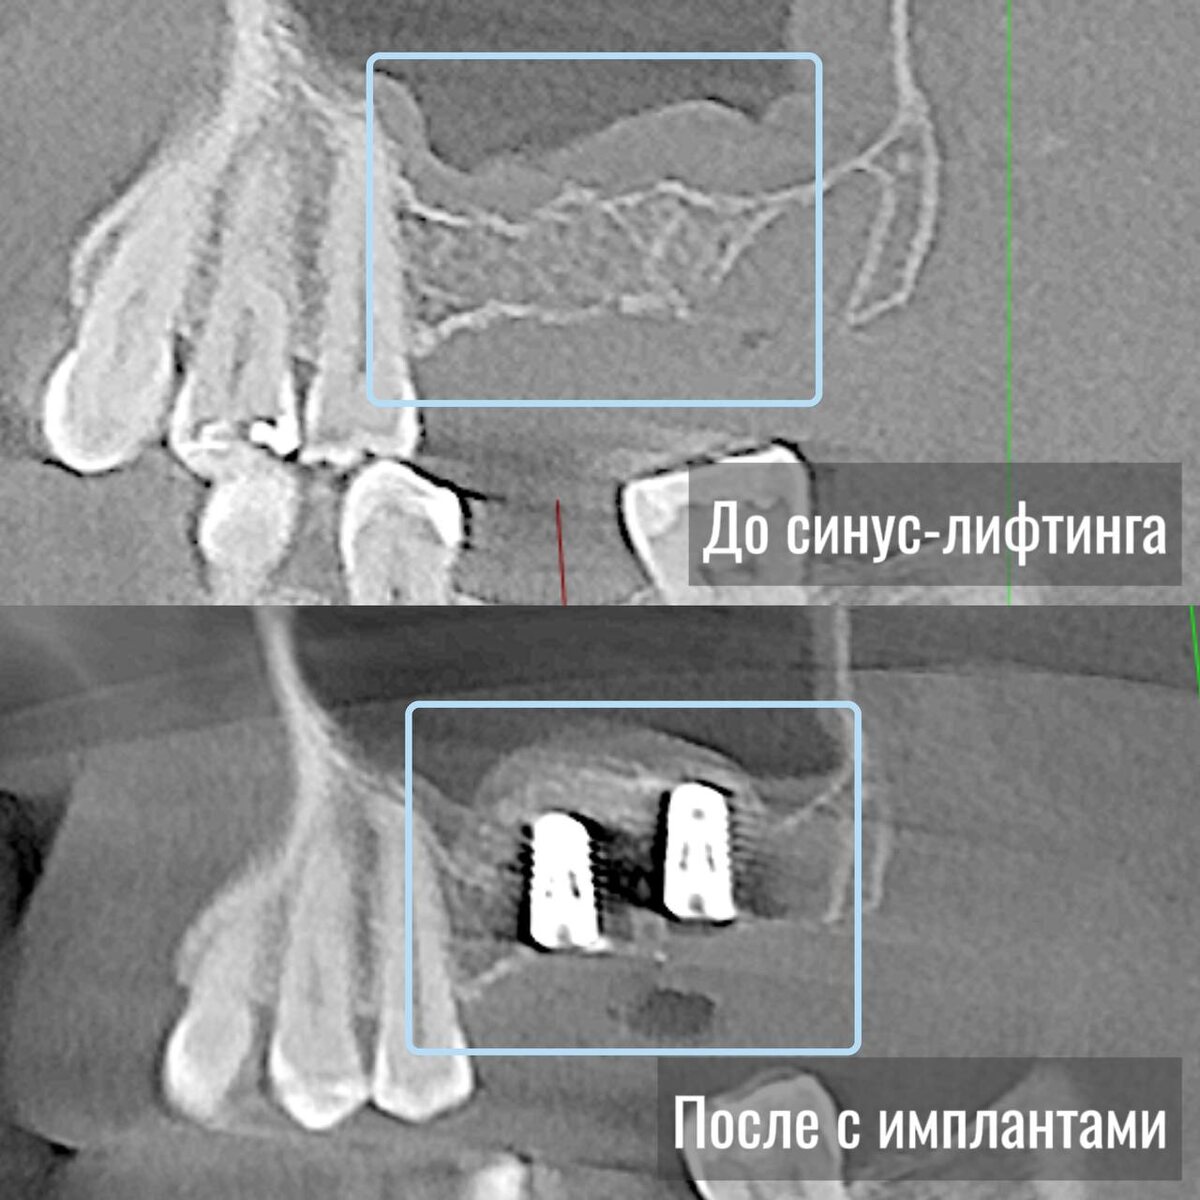

В прошлом посте мы говорили о костной пластике, а сейчас разберем, что такое синус-лифтинг Это манипуляция, при которой тоже добавляют количество костной ткани, но именно на верхней челюсти. Называется она так потому что рядом располагаются пазухи (синусы).  Синус-лифтинг или поднятие синуса – это хирургический процесс, который стоматологи используют для увеличения количества костной ткани в области верхней челюсти, в районе задних верхних зубов. Это может быть необходимым, когда пациенту требуется имплантация, но в данном месте недостаточно костной ткани для устойчивости и надежной фиксации имплантатов. В ходе данной манипуляции врач создает доступ к пазухе, мягко поднимает слизистую оболочку и добавляет костный материал в образовавшееся пространство. Это обеспечивает дополнительный объем для установки имплантатов спустя 4-6 месяцев поле имплантации #хирургия